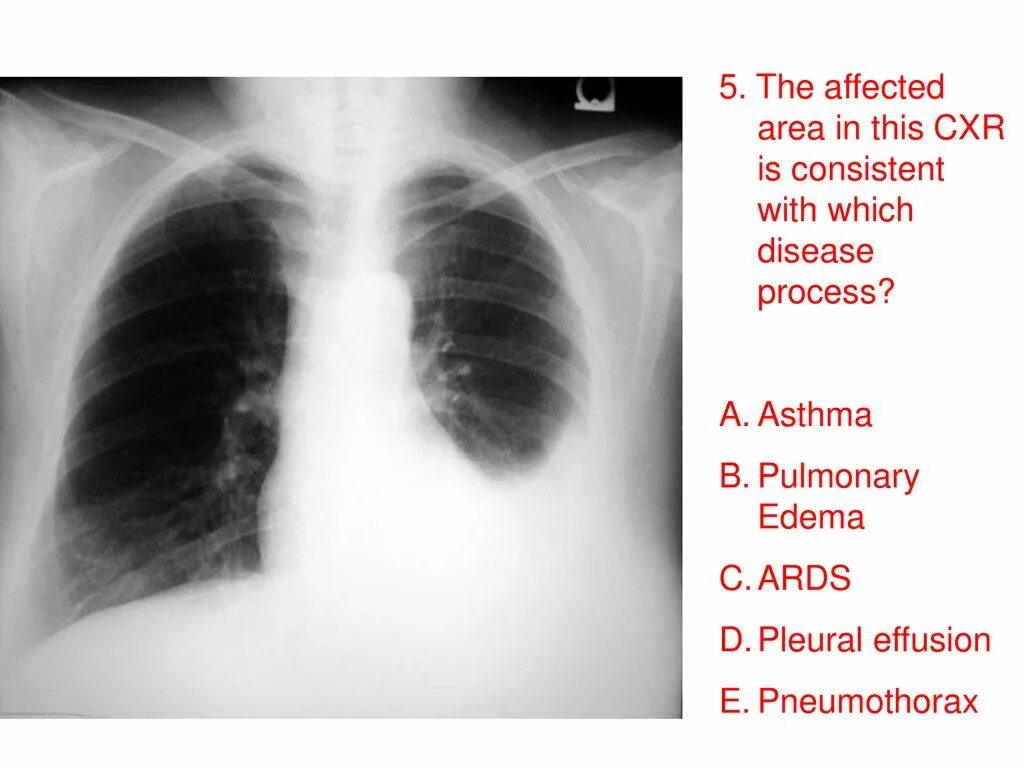

Метастазы плевры